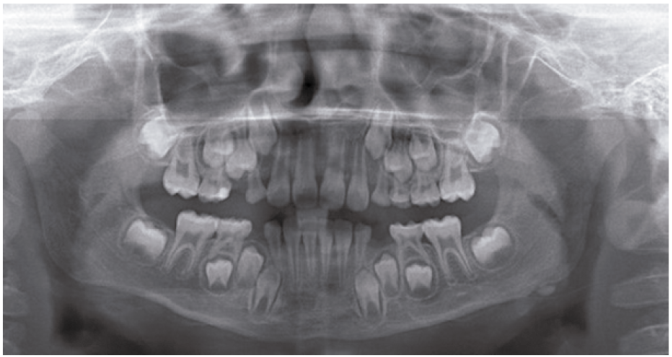

An 8-years-old boy reported to the Department of Oral and Maxillofacial Surgery, Ondokuz Mayis University with a chief complaint of hard swelling in the left posterior region of the mandible. The patient was physically healthy and any systemic condition was not detected during anamnesis. The swelling was not associated with any pain, discharge, fever, paresthesia, or difficulty in mastication. The patient did not recall or confirm any history of trauma or infection in that region. On clinical examination, a solitary, non-pulsatile and approximately 1.5 cm in diameter, bony mass was palpated at the left angle region of the mandible. The tumor found fixed to the underlying bone and the skin overlying the tumor was in a healthy appearance. The panoramic radiography and cone beam computed tomography (CBCT) scan showed a well circumscribed, radiopaque mushroom like image located on the left angle of the mandible (Figure 1, Figure 2). The 3D reconstruction of the computed tomography image revealed a pedunculated homogeneous bony mass attached to the left angle of the mandible (Figure 3). The lesion was completely excised using an extra oral approach under general anesthesia (Figure 4). The surgical specimen was submitted for histopathological examination. Histopathological examination revealed a sclerotic lamellar bone nodule with almost no intertrabecular space (Figure 5). These features confirmed the final histopathologic diagnosis to be peripheral osteoma. The post-operative course was uneventful with a satisfactory healing (Figure 6) . The patient is still under follow-up.